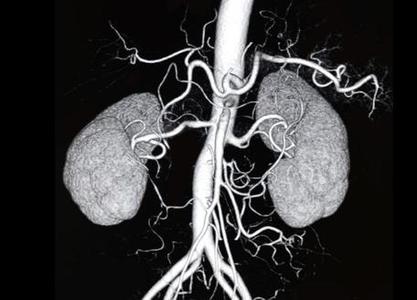

Eski cihazlarda kesit kalınlıkları 1cm civarında iken yeni nesil cihazlar ile 1 mm’nin altına inmiştir. Bu nedenle milimetrik boyuta bile ulaşmayan kitlelerin tanısı mümkün hale gelmiştir. Ayrıca bu cihazların hem görüntü kalitelerinin artmış hem de çekim sürelerinin azalmış olması nedeniyle damar yapılarının incelenmesine olanak sağlar hale gelmiştir. Günümüzde kalp, beyin, boyun, göğüs, karın ve bacakların damarları BT Anjiografi ile rahatlıkla değerlendirilebilmektedir. Konvansiyonel katater Anjiografi yerine daha az yan etkisi olan ve hasta için daha konforlu olan BT Anjiografi işlemleri sıklıkla tercih edilmektedir.